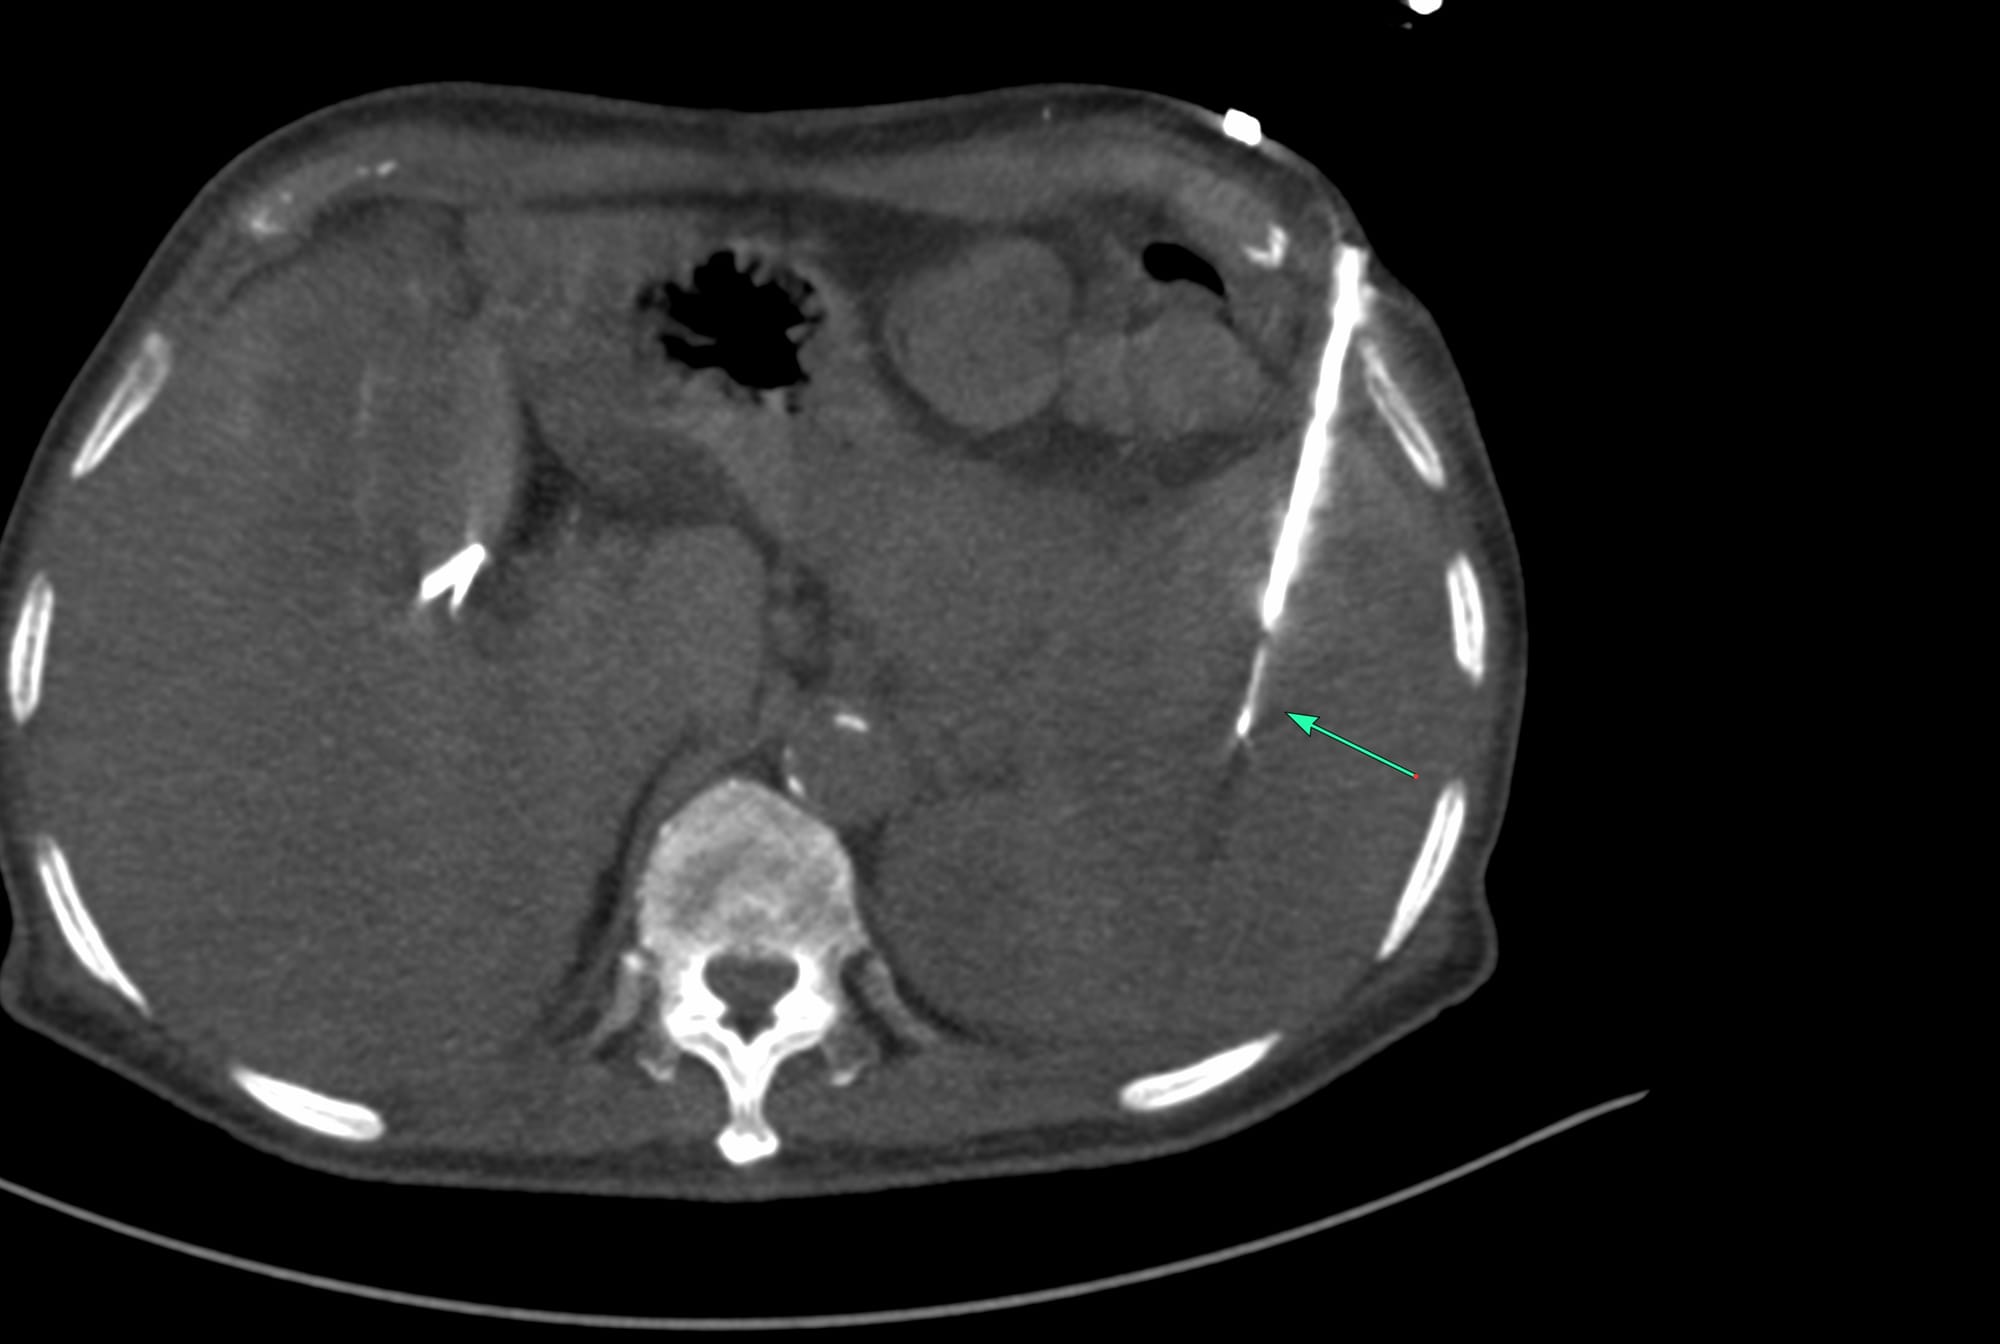

Case 164: Parting of the Bowel Loops with a Blunt-Tip